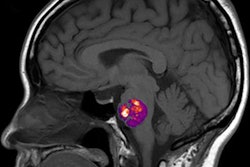

Trained using 414 patients clinically diagnosed with Alzheimer's disease and normal controls in the ADNI, the researchers' fully convolutional neural network (CNN) generates color-coded disease probability maps after analyzing T1-weighted brain MR images. Next, a multilayer perceptron analyzes these disease probability maps to produce a binary classification of Alzheimer's disease status.

In other results, the model's identification of high-risk cerebral regions closely tracked postmortem histopathological findings, according to the researchers.

"Not only can we accurately predict the risk of Alzheimer's disease but this algorithm can generate interpretable and intuitive visualizations of individual Alzheimer's disease risk en route to accurate diagnosis," Kolachalama said in a statement.